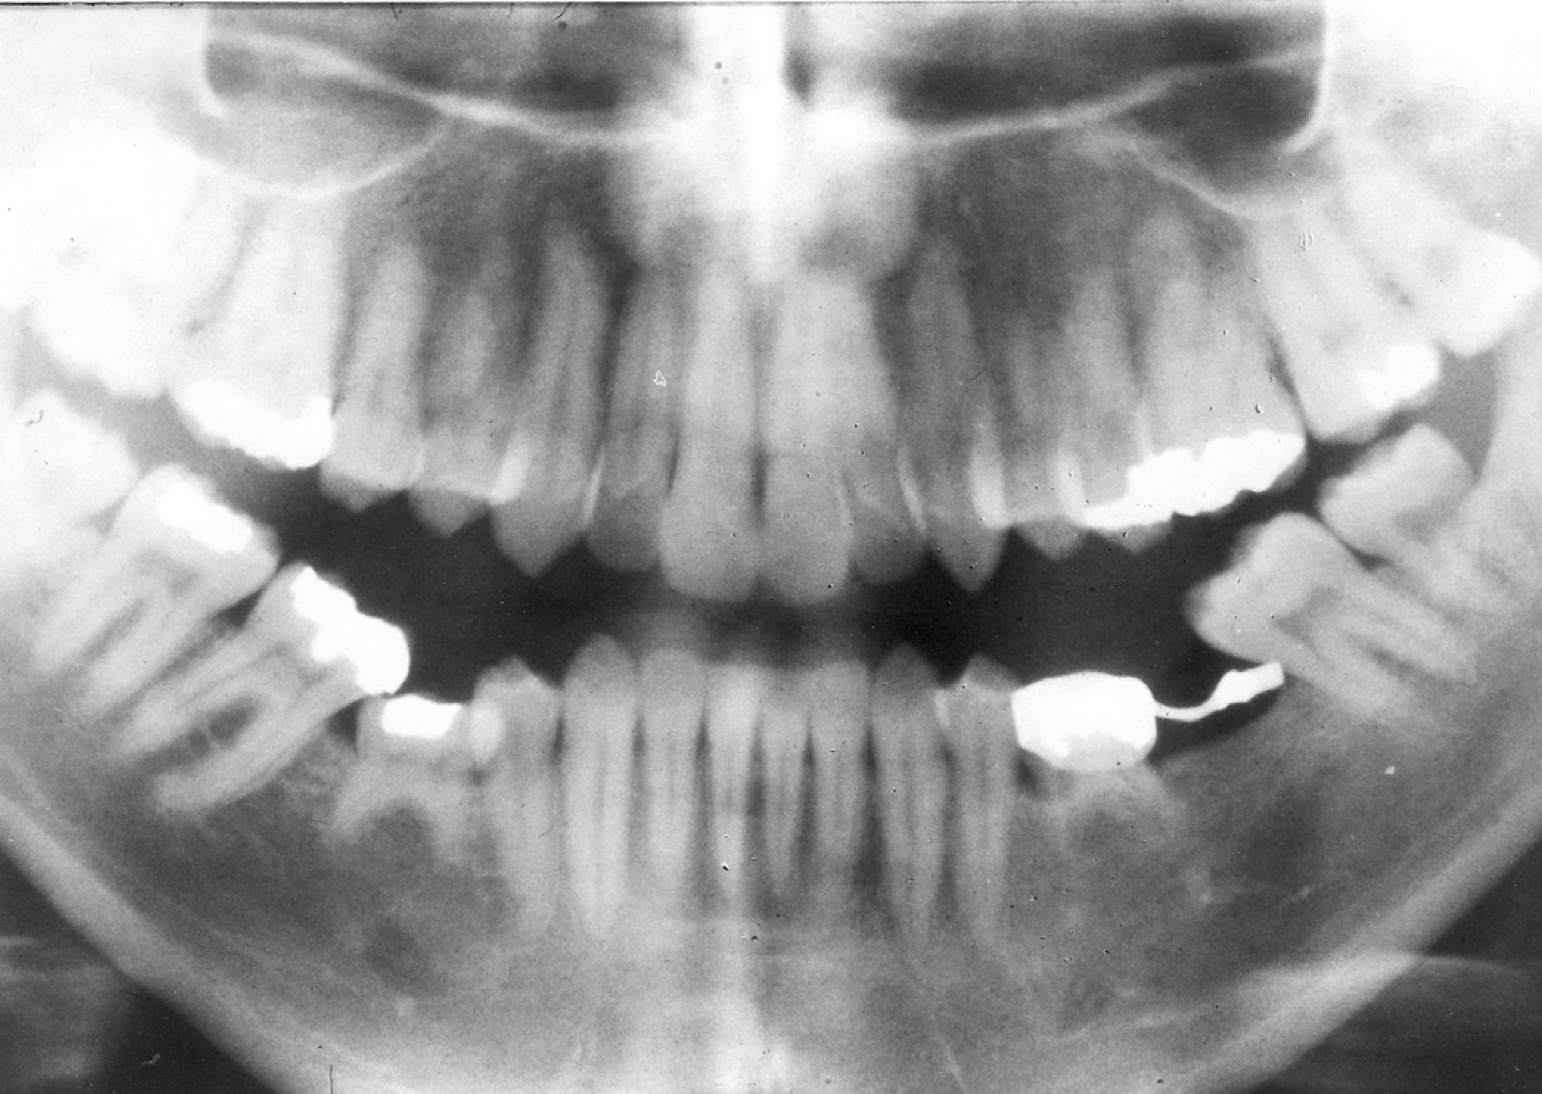

Amalgam materials – The first reported use of amalgam as a restorative material dates back to 659 AD in China. Amalgam is a substance that combines two or more different metals, usually silver, copper, zinc, and tin to form an alloy. This alloy is combined with mercury to make dental amalgam. Various groups have tried to have amalgam banned because of the toxicity of mercury in certain situations. Studies continue to show amalgam as a safe, affordable, durable, restorative material, backed by the American Dental Association and governmental agencies. Amalgam is still a common material used for dental restorations today (Figure 1).

Advantages of amalgam include its durability and long lasting restorations, ease of use in hard to reach areas, or in areas where isolation of fluids is a problem. It is time efficient, which is important when children are uncooperative. Disadvantages of amalgam include its color, concerns about mercury content, and the possible need for the removal of healthy tooth structure for mechanical retention. (For more information on mercury refer to the ADAA course Mercury in Dentistry - The Facts.)